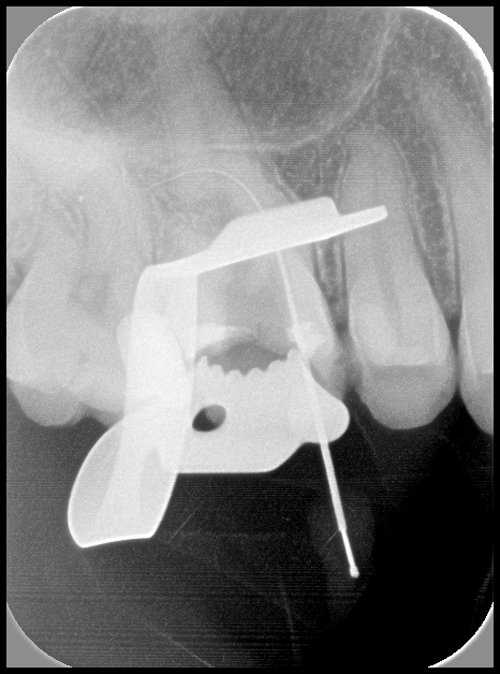

TRAITEMENT ENDODONTIQUE

Un traitement endodontique est réalisé lorsque des bactéries colonisent l’intérieur de la dent. Les canaux sont nettoyés selon un protocole précis. L’endodonte (intérieur de la dent) est ensuite obturé pour assurer la pérennité de cette désinfection (mécanique et chimique). Une fois les canaux remplis et étanches, un pansement provisoire est posé. La dent sera reconstituée de façon étanche et durable par le chirurgien-dentiste traitant. La dent sera reconstituée de façon étanche et durable par le chirurgien-dentiste traitant.